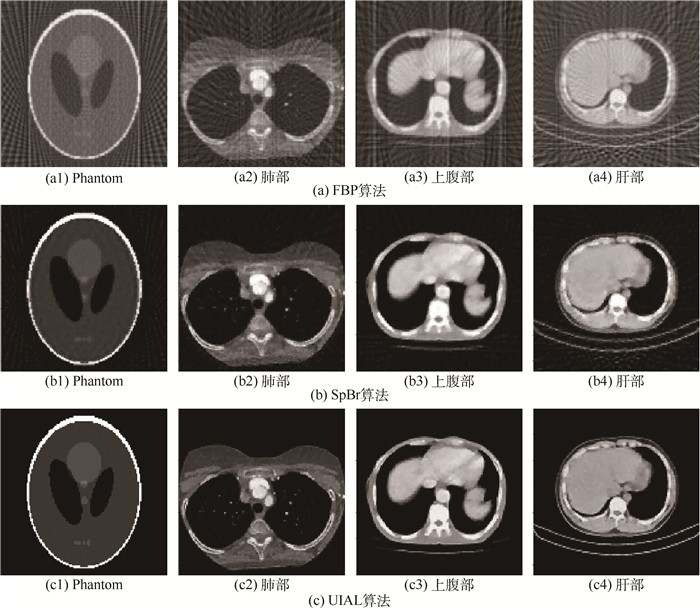

CT image reconstruction model and algorithm from few views

LIN Luping, WANG Yongge

2017, 43(4): 823-830. doi: 10.13700/j.bh.1001-5965.2016.0232

Abstract:

To improve the accuracy and efficiency of few-view computed tomography (CT) image reconstruction, CT image reconstruction is studied from limited view and sparse view, and a novel objective function of total variation norm is proposed. According to the newly-developed objective function, the next iteration is based on the information acquired in the previous one, through which the updated sparse representation model is achieved at each iteration. Additionally, the constrained optimization problem is converted to unconstrained optimization one by adopting the augmented Lagrangian method. Then it can be equally expressed by three sub-problems which can be solved by the alternating minimization scheme. The experimental results using the proposed strategy show that it can attain higher quality CT images which possess integral information, clear detail and high precision. Furthermore, the relative root mean square error can be reduced by 42.1%-98.5% and the streak indicator 42.8%-98.5%, compared with those using Split Bregman-based algorithm.